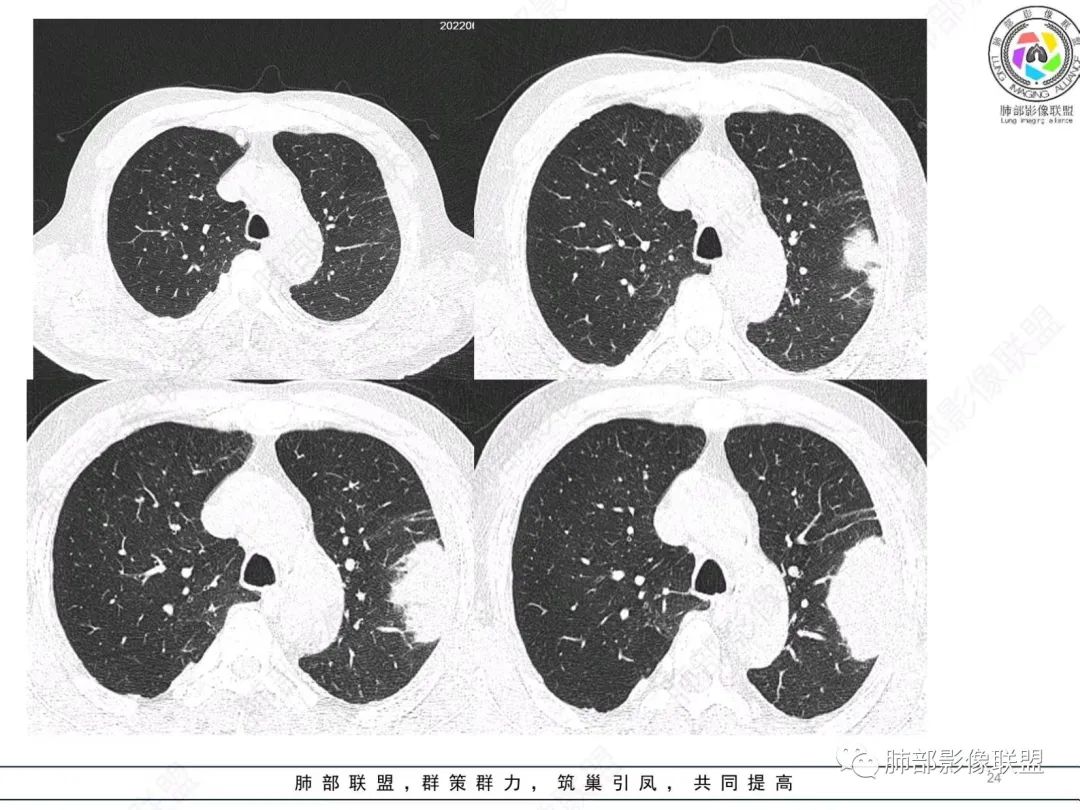

原发性肺肉瘤样癌(PSC)一组临床罕见的肺部肿瘤,属于上皮细胞源性肿瘤,仅占肺部恶性肿瘤的0.3%~4.7%。为含有肉瘤形态细胞或肉瘤样分化的非小细胞肺癌,癌成分多为鳞癌或腺癌,肉瘤成分最常见的是纤维肉瘤。

肺肉瘤样癌的CT表现主要特点:

1)部位:周围型或中央型软组织肿块,以周围型为多见,且肿瘤多位于肺上叶。如本例:该肿瘤位于左肺上叶。

2)大小及形态:由于本病恶性程度高,早期症状不明显,发现时肿块均较大。如本例病变巨大。

3)肿块边界和边缘:多较清楚,呈圆形、类圆形,且由于肿块生长速度不均匀,可见分叶,毛刺少见。有报道肿块周围毛玻璃影是多形性癌特征表现。

4)密度:肿块平扫为软组织密度,由于体积较大,内部常见大片状坏死,可出现不规则厚壁空洞或坏死内多发无壁小空洞,坏死多不均匀:坏死灶内可见如柳絮样的斑片样强化灶,坏死边缘与非坏死区分界不清本例坏死较明显,密度不均匀。

5)肿瘤强化方式:肺部恶性肿瘤强化程度与其血供丰富程度相关,血供丰富多强化明显,反之则较差。由于PSC 周边实性部分富血供及内部黏液变性、坏死,增强后肿块多数呈轻-中度边缘环形强化或不均匀小斑片状强化。国外学者对照病理发现肿瘤细胞或胶原组织增强扫描时强化,无强化的低密度区代表了黏液样变性区和出血坏死区。